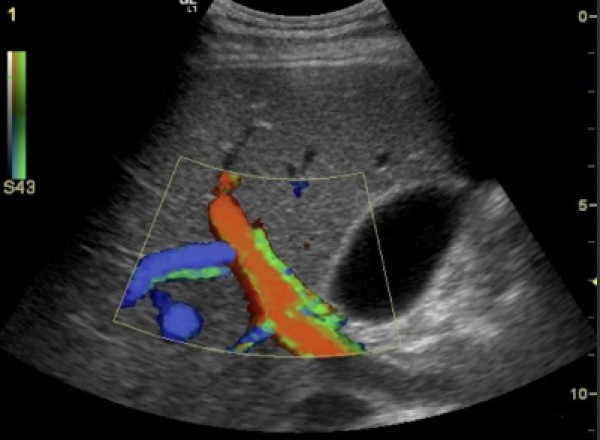

L'IMAGERIE : RADIOGRAPHIE, ECHOGRAPHIE et FIBROSCOPIE

La clinique dispose de matériels très performants qui participent au diagnostic, au dépistage et au suivi de très nombreuses pathologies.Ils servent également au diagnostic de gestation et au suivi optimal des chatons et des chiots.

La salle radio est entièrement plombée et possède une développeuse automatique garante de qualité.L'échographie et la fibroscopie sont assurées par des appareils très efficaces (General Electric et Fujinon).